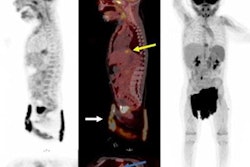

I-123 MIBG–negative and F-18 MFBG–positive scans showing multiple lesions in 9-year-old male with relapsed high-risk, multiple-relapse neuroblastoma (stage IV disease) receiving chemoimmunotherapy. (A) I-123 MIBG uptake is seen in lower lumbar vertebrae (arrows). Positive uptake with F-18 MFBG PET (B; black arrows) in skull, spine, pelvic bones, femora, and left tibia (B and C; blue and white arrows). Bone marrow biopsy was positive for disease. Follow-up I-123 MIBG imaging (D; left) and spine MRI (D; right) performed six weeks later showed diffuse disease in skull and spine, corresponding to F-18 MFBG–avid sites. Journal of Nuclear Medicine

Overall, more lesions were noted on the F-18 MFBG scans (mean, 18; range, 0-61) compared with the I-123 MIBG scans (mean, 12; range, 0-44), and 455 lesions were concordant. Finally, the Curie score (a measure of tracer uptake) for F-18 MFBG was higher, with an average of 11 (range, 0-25) compared with 8 for I-123 MIBG (range, 0-22), the group reported.